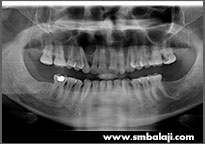

X-ray showing two impacted lower canine teeth

X-ray taken before extraction of upper right third molar tooth